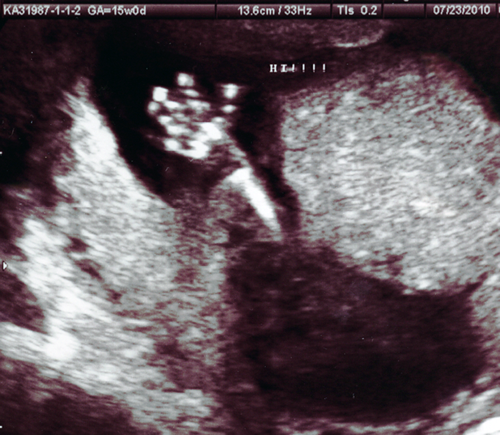

us_4

practicing his wave